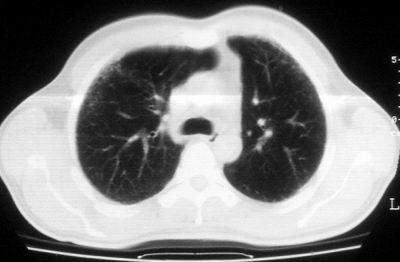

双肺散在小结节影,考虑粟粒性肺结核.肺窗薄扫会更好看些.

双肺外侧带胸膜下可见网状阴影,考虑轻度肺间质纤维化。

双肺纹理增强并可见网格状影达外带,考虑双肺感染并轻度间质纤维化

肺间质纤维化并肺部感染,结合不能排出,毕竟糖尿病人易合并之,建议结合ppd检查或hrct进一步扫描。